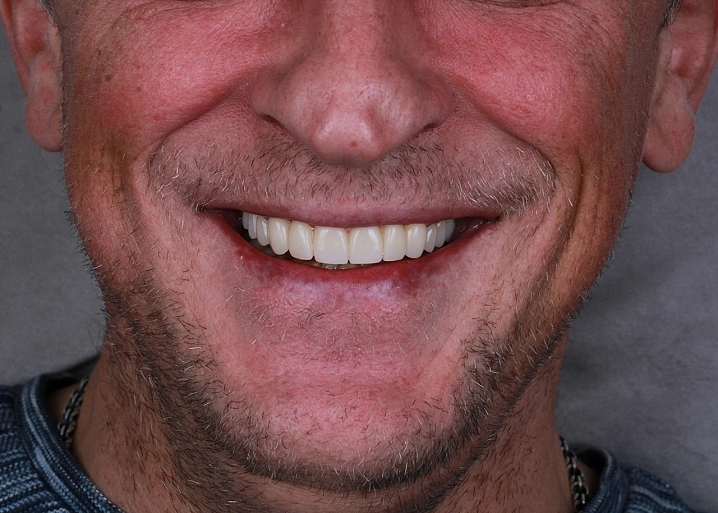

Полное восстановление происходит через 4-6 месяцев и можно приступить к установке имплантатов или к постоянному протезированию. Процедуру синус-лифтинга возможно провести с одновременной установкой импланта. Благодаря этому сокращаются сроки лечения на несколько месяцев.